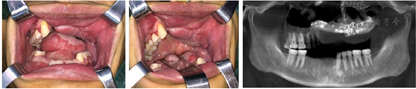

受伤当日排除手术禁忌后急诊全麻下行气管切开术、颌面部多发性骨折切开复位内固定术、左眼外伤探查术、颌面部外伤清创缝合术,由于患者已经出现呼吸道梗阻表现,且口腔内伤情复杂,为保证安全,我们首先进行气管切开,术中探查颌面部软组织外伤、左眼外伤及颌骨骨折情况,尽量按照解剖结构复位骨折断端,摘除左眼眼球,依次缝合面部及口内伤口(图2,图3)。术后根据患者病情送入ICU继续治疗,待病情平稳后转回我科继续治疗,正常出院。

患者伤后6个月入院,本次主要解决上颌骨缺损与口腔上颌窦瘘的问题,术前根据患者的颌面部CT及双下肢CTA采用数字化方法制作颌骨缺损模型、腓骨取骨导板、塑形导板及复位导板,并在颌骨缺损模型上提前将钛网进行塑形。全麻下行上颌骨内固定装置取出术、血管化腓骨游离移植术、上颌骨重建术、口腔上颌窦瘘修复术。术中将游离腓骨按手术计划放置于合适位置,固定后再将钛网覆盖于表面,起到支持上颌骨前壁的作用,同时使用腓骨瓣皮岛修复口腔上颌窦瘘(图4,图5,图6,图7)。术后给予抗感染、补液扩容、防血管痉挛及全身支持治疗,正常出院。